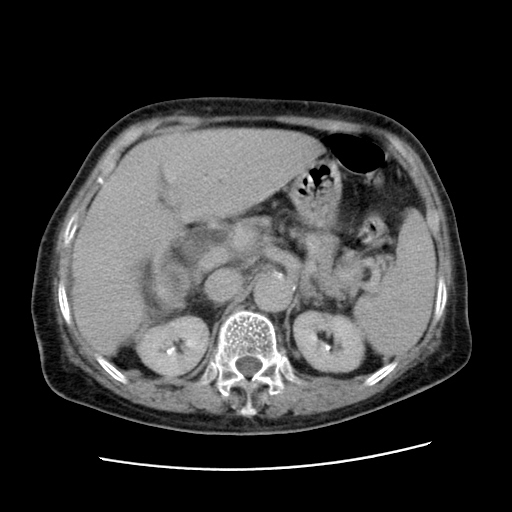

标题: CT25203:上腹部增强,看看

女,77.无不适

肝内胆管扩张,胆囊炎,胆囊窝积液。 右侧胸腔少量积液。

肝右叶肝内胆管结石并肝内胆管扩张。另:慢性胆囊炎!胆囊窝积液!

肝右叶肝内胆管结石并肝内胆管扩张。胆总管下段梗阻,考虑壶腹部占位。